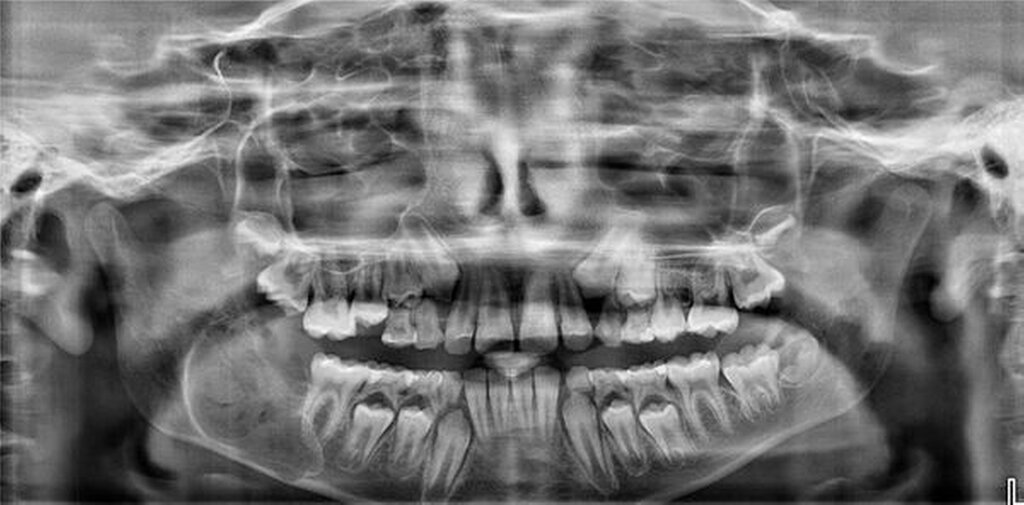

Zur Vorstellung brachte der Patient eine von seinem Hauszahnarzt angefertigte Panoramaschichtaufnahme mit, auf der sich der Zahn 47 retiniert und nach kaudal verlagert zeigte (Abbildung 1). Des Weiteren befand sich im Bereich des rechten Kieferwinkels eine ausgedehnte rundliche Verdichtung mit transluzentem Randbereich. Diese Raumforderung stand in direktem Kontakt zur Krone des retinierten und verlagerten Zahnes 47. Der Canalis mandibularis stellte sich nicht dar.

Anamnestisch berichtete der Junge von keinerlei Einschränkungen, Schmerzen oder sonstigen Auffälligkeiten. Im Rahmen der klinischen Untersuchung zeigten sich zudem keine Auffälligkeiten im Bereich des N. alveolaris inferior / N. mentalis rechts. Intraoral war die Schleimhaut im Bereich des Kieferwinkels intakt, ohne Anhalt für eine entzündliche Veränderung. Palpatorisch stellte sich eine dezente, schmerzlose knöcherne Auftreibung vestibulär dar. Zur weiteren Diagnostik und OP-Planung wurde eine digitale Volumentomografie angefertigt.